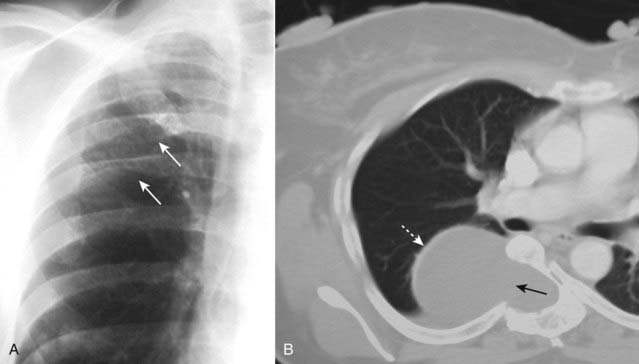

imageThe findings may be unilateral or may involve only one lobe, which should alert you to suspect the possibility of lymphangitic spread rather than congestive heart failure, which is usually bilateral (Fig. 12-19).

image

Figure 12-19 Bronchogenic carcinoma with lymphangitic spread of tumor.

In lymphangitic spread of carcinoma, a tumor grows in and obstructs lymphatics in the lung producing a pattern that is radiologically similar to pulmonary interstitial edema from heart failure. The findings may be unilateral, as in this case, which should alert you to the possibility of lymphangitic spread rather than congestive heart failure. There is extensive hilar and mediastinal adenopathy (solid black arrows) from a carcinoma of the lung. The interstitial markings are prominent in the right lung compared to the left, and there are thickened septal lines (Kerley B lines) present (solid white arrows) along with a right pleural effusion (dotted black arrow).